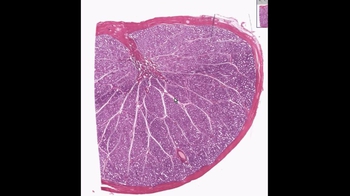

27. The Reproductive System

Anatomy of the Male Reproductive System

Male Reproductive structures